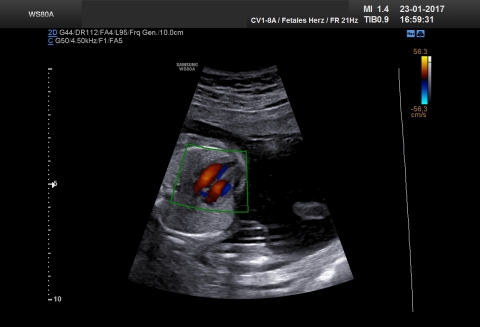

21. Woche